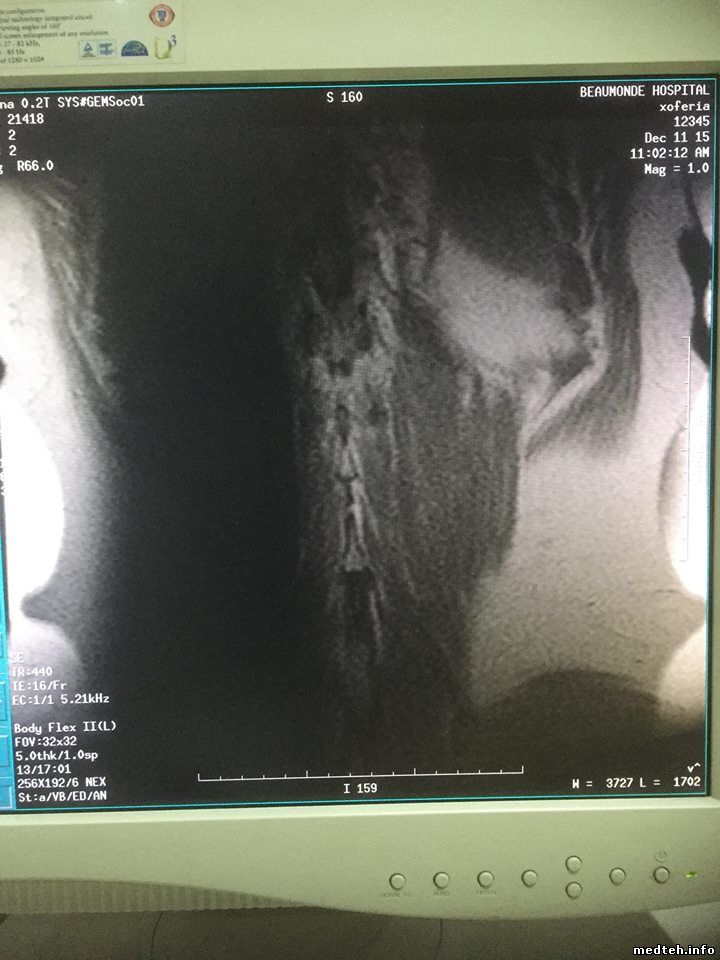

на продольном боковом срезе брюшной полости (катушка BodyFlex ) рядом с позвоночником слева вертикалный дефект картинки в виде темной полосы с размытыми краями... причина?

картинки такие:

1400157.jpg (85.3 Kb) · 5506200.jpg (95.1 Kb) · 2307948.jpg (156.9 Kb) · 2009293.jpg (158.7 Kb)

на мой взгляд, это потеря сигнала из-за наложения срезов.. смотреть чисто геометические параметры: матрицу, размер вокселя, расстояние между срезами, толщину среза.

Коллеги, закрадывается у меня мысль, что это очень напоминает сатуратор, который случайно выставили и забыли, насколько помню есть сатураторы которые не отображаются в виде сеточки, их просто в самом протоколе можно активировать и задать координаты, а тут просто как будто активировали и по умолчанию выставилась координата. Точно знаю, что на сосудах есть такие сатураторы, чтобы допустим, отсекать сигнал от вен и получать сигнал только от артерий. По маркировке, если память не изменяет по направлению фазы кодирования, ну что-то типа А или S. Попробуйте посмотреть в настройках самого протокола. Я ведь правильно понял, что это только в этой программе, такая фигня?

Да вроде на картинке пишет, что аж 3000 TR...

Мля, это какой-то добрый человек перекрутил сагиттал с сатуратором на потрохах в коронал. Не выключая сатуратор.